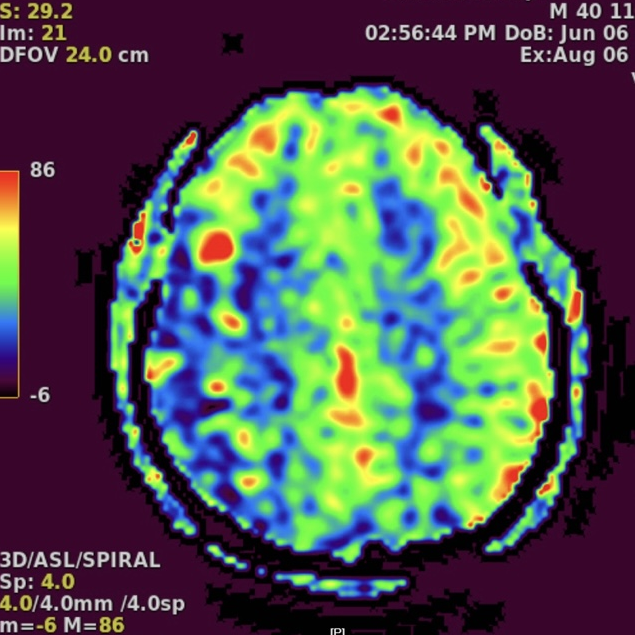

DSA提示患者右侧大脑中动脉狭窄率约95%;PWI提示右额颞顶叶低灌注。

动脉长鞘怎么置入一技之“长”丨经桡及经股困难入路应用赛诺神畅APEX TRA GC™导引导管建立通路病例合集_https://www.jmylbn.com_新闻资讯_第26张

头颅CT

头PWI